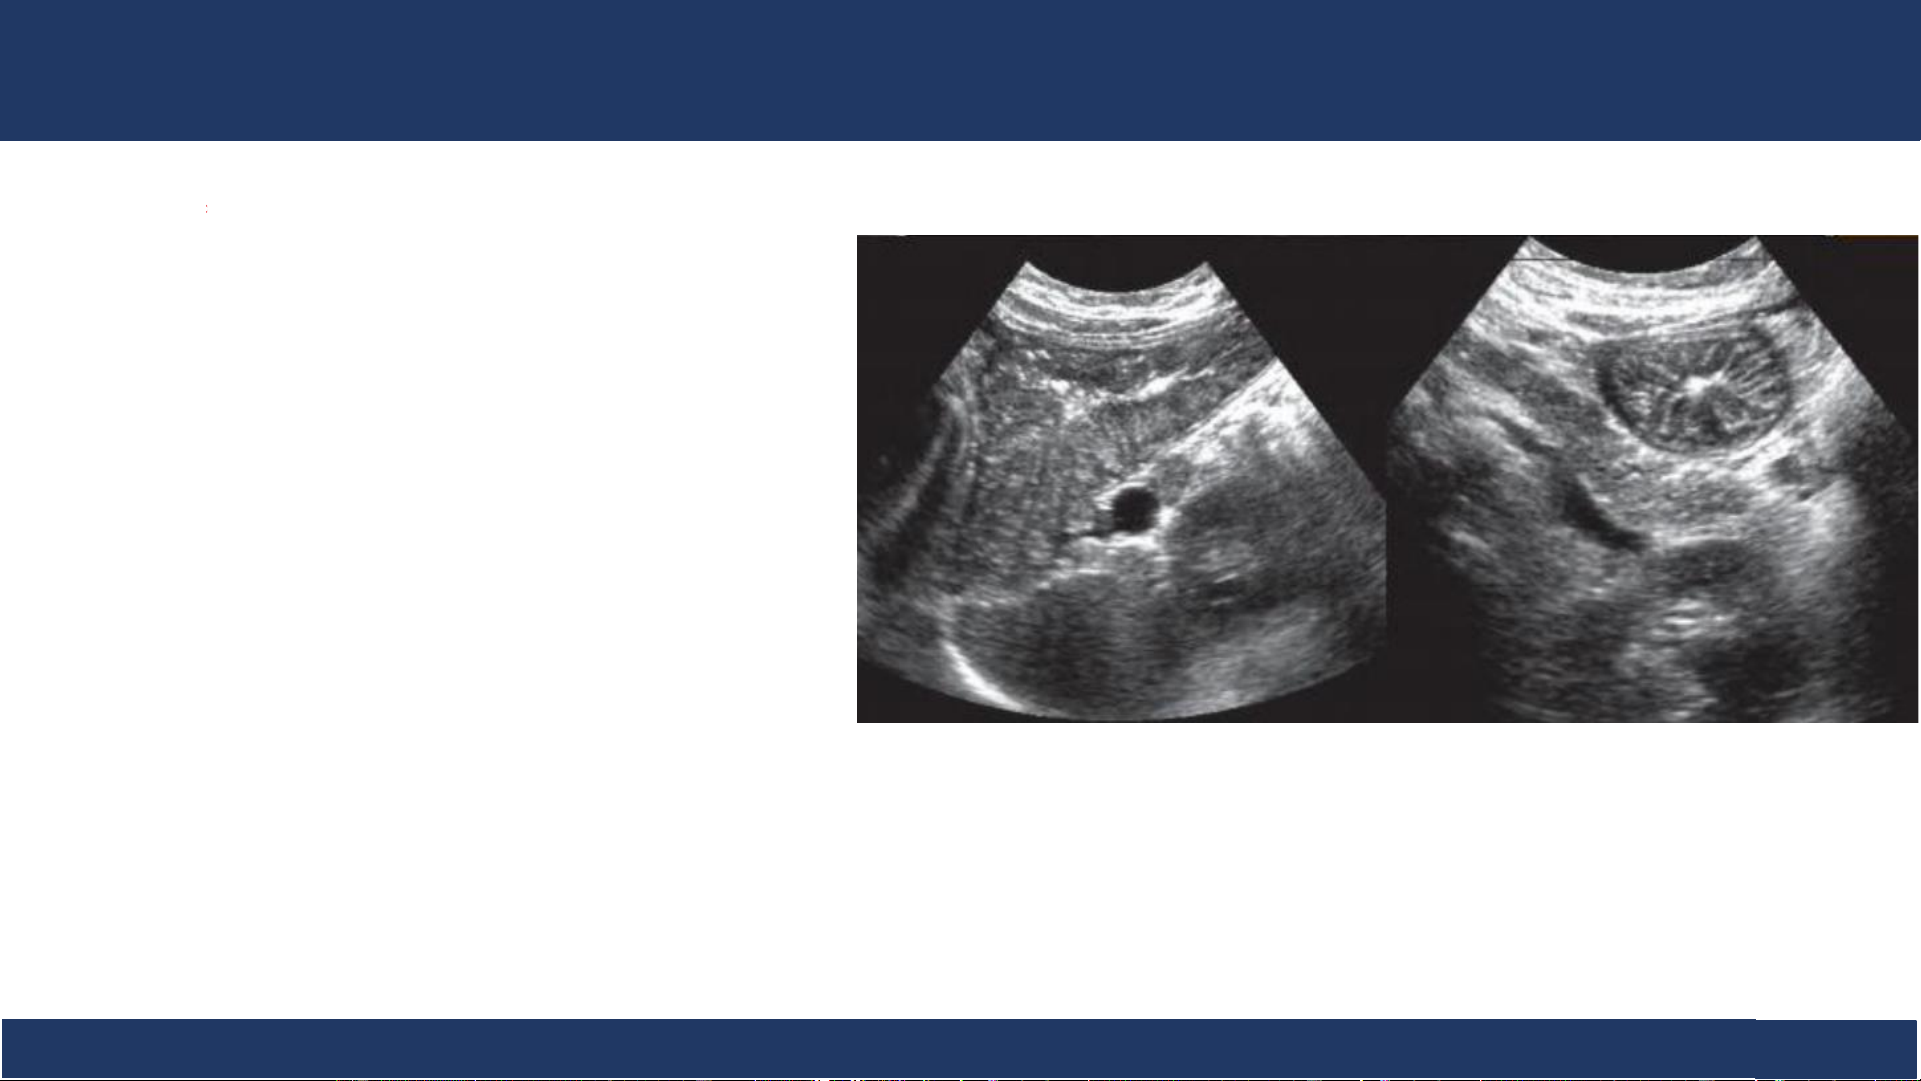

hình ảnh, ĐHYD TPHCM 14 SA: ruột non . Siêu âm ống tiêu hóa (ruột non)cho thấy các lớp niêm mạc, dưới niêm, cơ và thanh mạc Cắt ngang Cắt dọc Bệnh v B iệ ộ môn n Nh Chẩ i Đồng n đoán 1

hình ảnh, ĐHYD TPHCM 15 SA: ruột non

• Ruột non thường chỉ quan .

sát được từng đoạn và không

xác định được vị trí trừ đoạn cuối hồi tràng. • Tùy trạng thái:

✓ Xẹp hoàn toàn: thấy rõ hai thành với lớp dịch mỏng ở trung tâm.

✓ Có chứa dịch tiêu hóa lẫn khí và nhu động

✓ Hơi có từng mảng dài, vô định hình.

✓ Nếp niêm mạc vòng đồng tâm, mỏng và nhặt (ruột căng ứ dịch). Bệnh v B iệ ộ môn n Nh Chẩ i Đồng n đoán 1